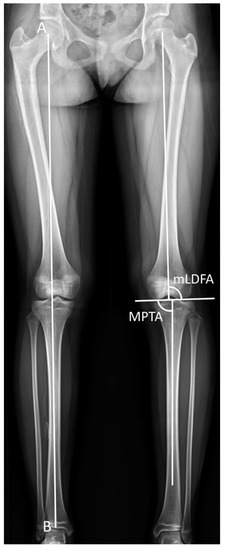

The latest postoperative radiographic measurements including the mLDFA, MPTA, and MAD are summarized in Table 3. The mean postoperative mLDFA was 85.0° (range, 79.5°–91.0°) in Group 1 and 86.5° (range, 80.0°–93.4°) in Group 2. The mean postoperative MPTA was 86.4° (range, 80.2°–93.5°) in Group 1 and 87.6° (range, 81.3°–93.5°) in Group 2. The postoperative MAD, the indicator of lower-limb malalignment, was 14.2 mm (range, 1.0–46.0 mm) in Group 1 and 6.7 mm (range, 3.0–13.0 mm) in Group 2. All in all, the postoperative mLDFA, MPTA, and MAD of Group 1 were not distinguishable from Group 2. The case of an 18-year-old girl with hypophosphatemic rickets who underwent acute angular correction and fixator-assisted lengthening is demonstrated in Figure 2 and Figure 3 at 40 months follow-up.

Figure 2. Anteroposterior radiographs of an 18-year-old girl who underwent fixator-assisted plating and acute angular correction for leg-length discrepancy. (a) A preoperative anteroposterior view of the tibia. (b) The procedure was conducted using an Ilizarov apparatus and a submuscular plate. (c) Satisfactory tibial lengthening and alignment were achieved. (d) The distal part of the submuscular plate was fixed at removal of the external fixator. (e) The distracted callus healing with good consolidation was seen in the latest radiograph 40 months after the operation.